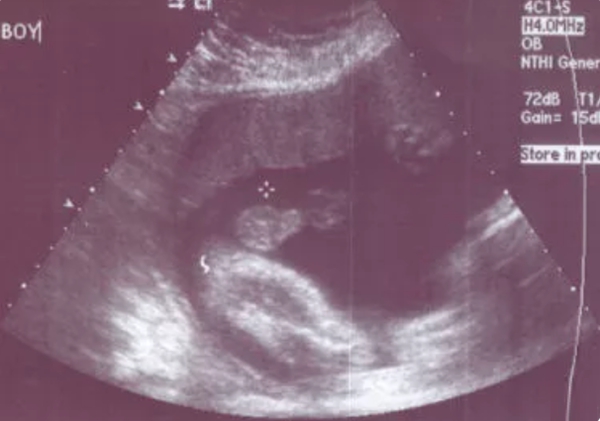

对于泰国试管婴儿相信大家都会有这样的一个疑问,那就是泰国试管婴儿移植的时候,胚胎都放在子宫哪里了呢?是放在子宫中间还是子宫深处呢?让我们一起来了解下.

不良的胚胎移植技术会损伤子宫内膜、诱发子宫收缩和将胚胎放置在种植欠佳的位置,从而降低种植率.成功的胚胎移植依赖于将胚胎无创伤地放置在有最大种植潜能的子宫中部.有数据表明,使用软导管可将子宫内膜损伤最小化,通过移植实现"轻松"胚胎移植,最大限度地降低子宫收缩的技术以及超声引导实现了靶向的、理想的胚胎放置位置.因此,子宫的位置以及放置胚胎的位置是影响成功胚胎移植的关键因素.

医生可能会告诉你:胚胎是会乱跑的,它会自己选择想要待的地方,所以万一它要是种植在了子宫瘢痕的地方,或者溜出去跑到输卵管里,所以说,泰国试管婴儿也会发生宫外孕的机率;但是如果是囊胚胚胎就避免了宫外孕的发生,囊胚是发育比较成熟的胚胎,输卵管容不下他溜进去安家,所以移植囊胚能提高试管的成功率,降低宫外孕的发生,泰国试管婴儿移植的一般都是囊胚.